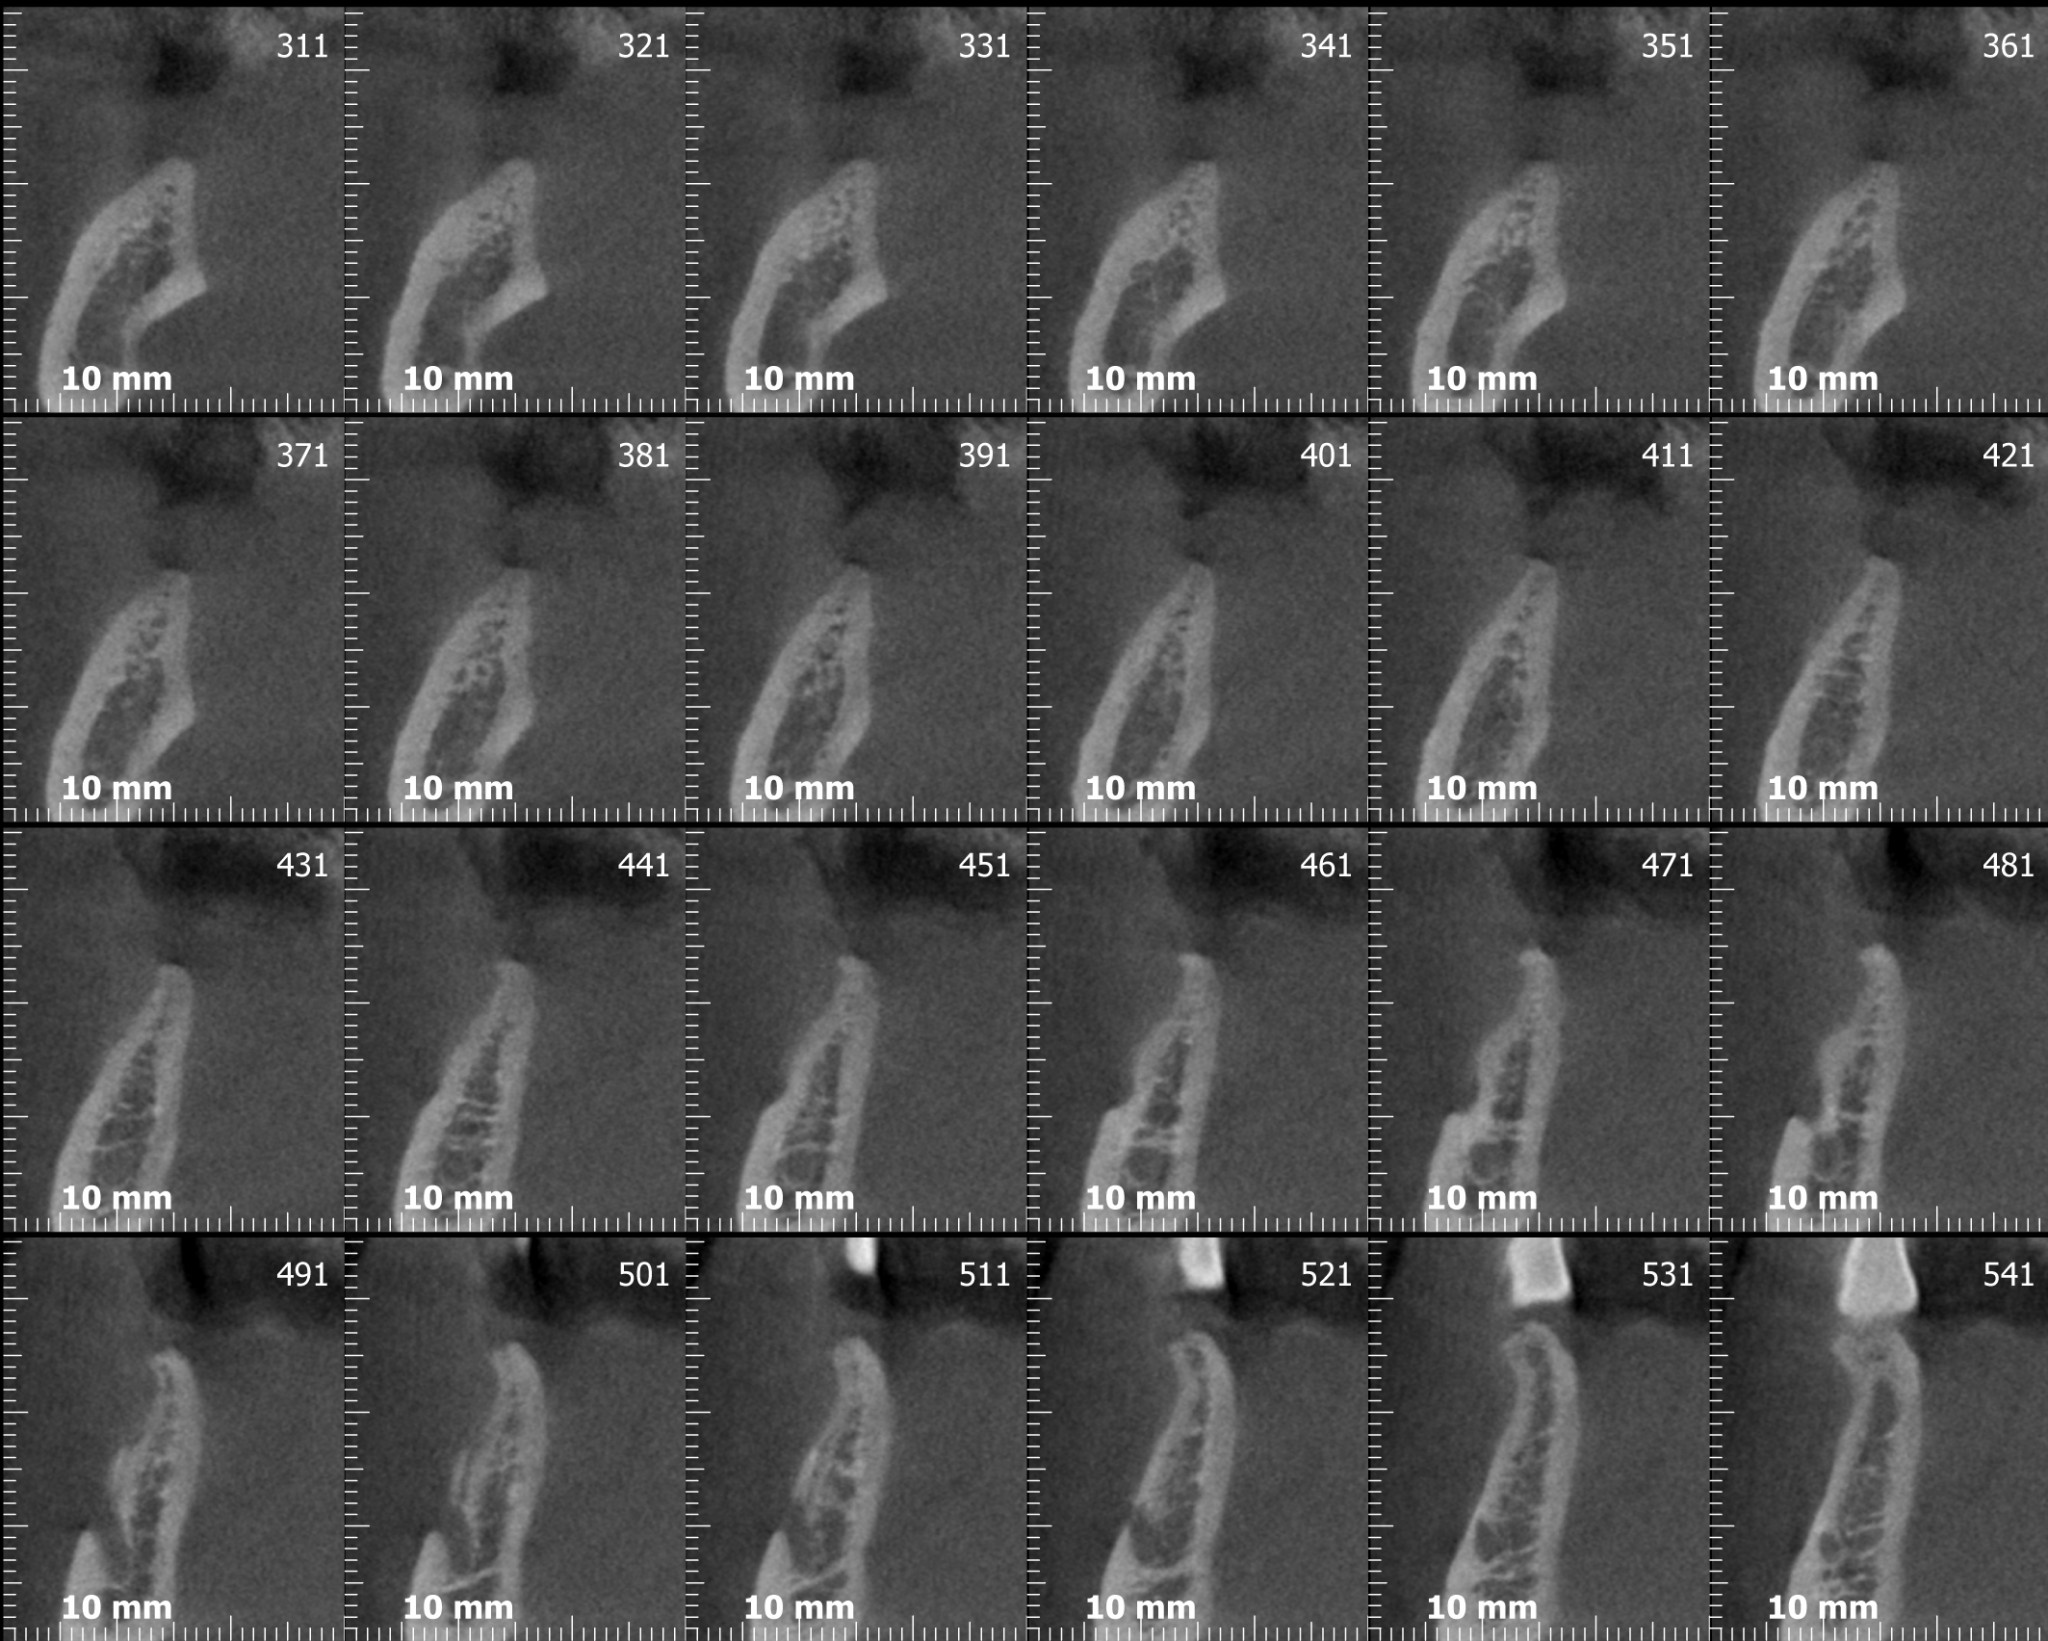

Adesso andiamo a vedere la cone-beam che sicuramente, secondo qualcuno, si sarebbe potuta evitare….

Se avessimo messo un impianto da 10mm nella zona del sesto con un asse protesicamente corretto avremmo proiettato tre o quattro millimetri delle nostre frese rotanti nella loggia sottomandibolare con tutti i danni potenziali che questi avrebbe potuto generare (se non l’hai ancora fatto vai poi a leggere l’articolo che ho linkato prima!).

Avevi notato questo? Dai tagli della cone-beam si nota chiaramente una variante anatomica abbastanza importante: un foro mentoniero accessorio posizionato più o meno a metà tra la cresta e il foro primario, diciamo circa 7 mm apicalmente alla cresta, dal quale emerge un ramo di diametro rilevante del nervo alveolare inferiore. Chissà a quale parte del mento o del labbro porta le sensibilità quel piccolo ramo!? Diciamo che per mantenere immacolato il mio palmares medico legale preferisco non scoprirlo!